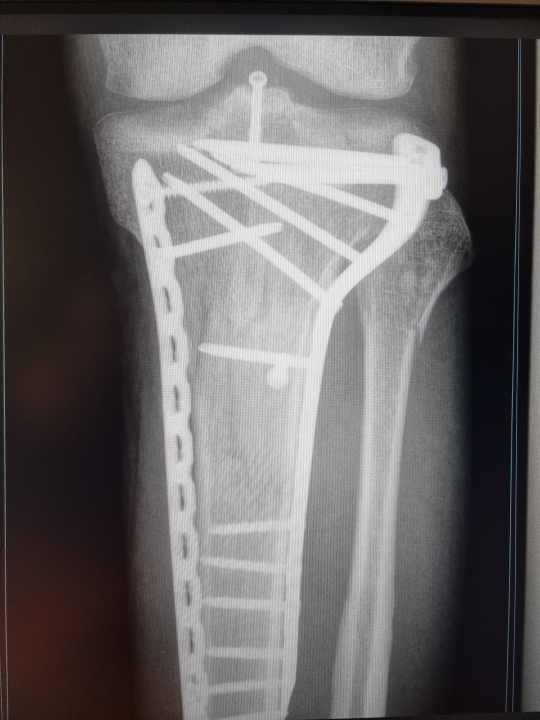

Betroffene kennen das Problem: Nach einer Verletzung des Kniegelenks ist der Weg zurück aufs Bike oft ein steiniger. An einem gewissen Punkt setzen Therapeuten den Verletzten auf ein Ergometer mit verkürzter Kurbel. Der erste Schritt zurück zur Biker-Normalität und doch, im geschlossenen Raum einer Reha-Einrichtung, gefühlt unendlich weit weg von der geliebten Sportart. Einigen engagierten Bikern reicht der meist kurze Moment auf dem stationären Rad nicht. Sie wünschen sich eine Lösung, um auch auf dem normalen Bike etwas für ihr Knie zu tun. Andere erwischt es schlimmer und die Beweglichkeit des Gelenks braucht Jahre, um akzeptable Ausmaße zu erreichen.

Kurbelverkürzungen helfen Patienten nicht nur ihr Bike trotz fehlender Kniebeweglichkeit zu nutzen, sie entlasten auch Knie und Hüfte. Spezielle Kurbeln mit einer einseitigen Verkürzung sind nicht nur schwer zu finden, sondern auch oft teuer. Andreas Sextl von Wexelpunkt wollte das nicht akzeptieren und startete 2021 mit der Entwicklung eines Adapters, der jedes Fahrrad zum Reha-Gerät machen könnte. Mit seiner Erfahrung als Physiotherapeut und Sportler sowie dem Feedback seiner radfahrenden Patienten will Sextl den Kurbeladapter nun zur Serienreife bringen. Seit Juli 2023 ist seine Lösung international rechtlich geschützt. Ab dem Frühjahr 2024 sollen die ersten Wexelpunkt-Adapter ausgeliefert werden. Eine Vorbestellung ist über anfrage@wxvario.de möglich. Kostenpunkt pro Stück: 169 Euro. Das Umrüstkit für die Verwendung rechts oder links kostet 59 Euro. Mehr Infos unter: www.wexelpunkt-wxvario.de